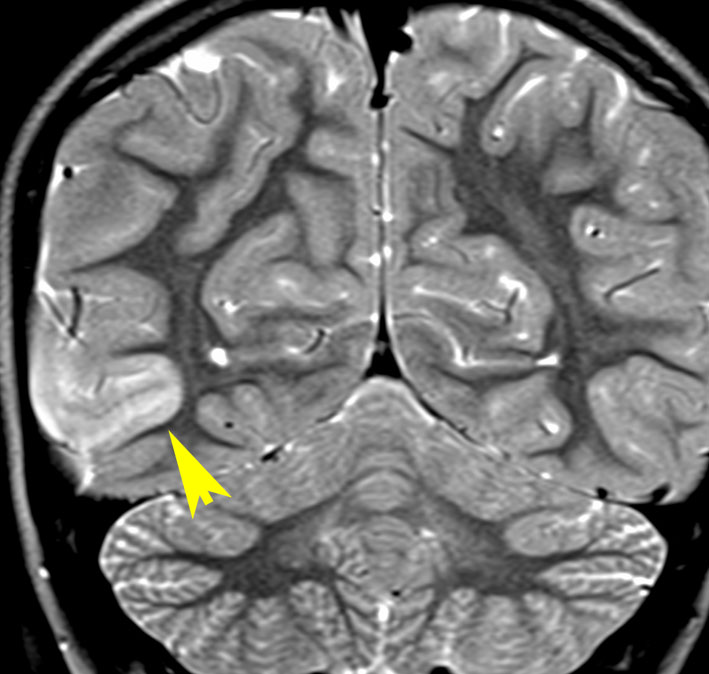

新生児期にてんかん発症した例 focal cortical dysplasia 2b

右頭頂葉の皮質異形成です。生後2週間目に両上肢を挙げるような発作を生じて難治化,1歳を超える頃には発達の遅れが目立ちました。新生児期にはMRIで描出できなかった病変が1歳になって初めて写るようになりました。手術で病変摘出 lesionectomy して投薬中断ができて,その後は普通に育ちました。